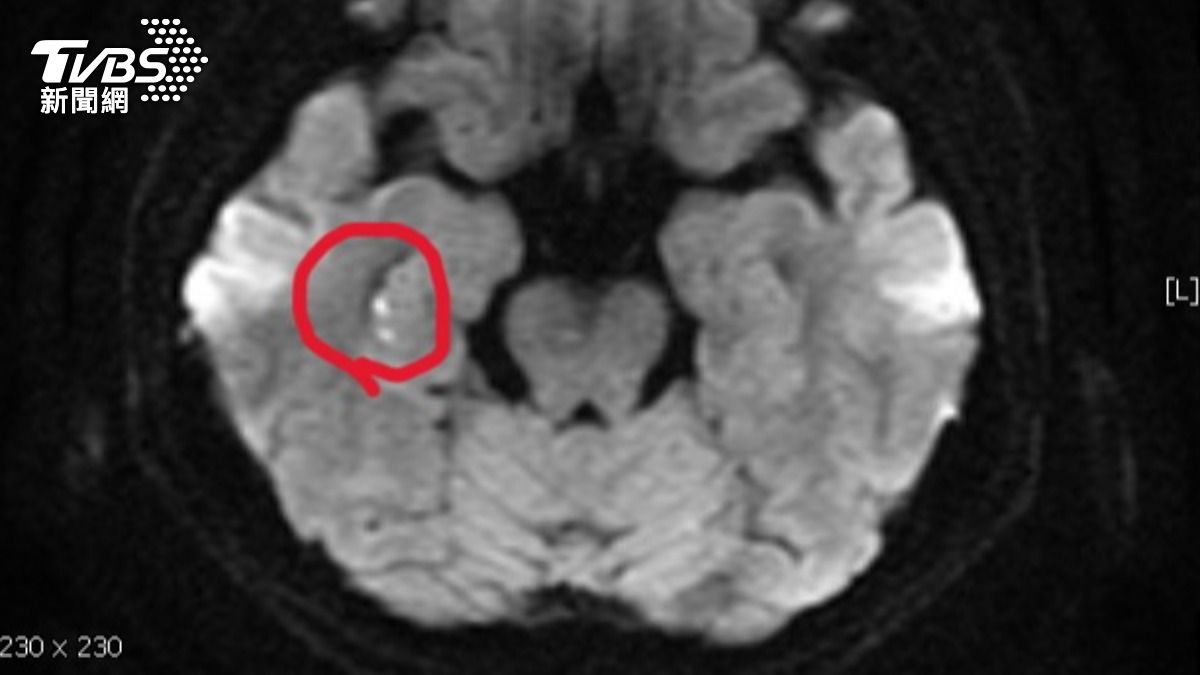

陳醫師表示,患者接受腦波檢查是正常;但核磁共振,看到她右側海馬迴出現一點亮亮的影像。海馬迴與記憶功能密切相關,證實她「短暫性全面失憶」狀況,是因為情緒過於激動,中風所造成。